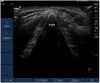

Methods: In a prospective observational study, anaesthetists were asked to locate the CTM by palpation which was then identified using ultrasound and the distance between the actual and estimated margin of the CTM was measured. Participants assessed the ease of CTM palpation using a visual analog scale. In a second series, the angulation of the posterior junction of the thyroid laminae was measured using ultrasound.

Results: 23 anaesthetists and 44 subjects participated. A total of 36 assessments were carried out in each gender. Incorrect identification of the CTM was more common in females (29/36 vs. 11/36, P < 0.001) and the distance from the CTM in the vertical plane was greater (11.0 [6.5-20.0] vs. 0.0 [0.0-10.0] mm, P < 0.001). In females distance from the CTM correlated positively with neck circumference (P = 0.005) and BMI (P = 0.00005) and negatively with subject height (P = 0.01). Posterior thyroid cartilage angulation was greater in females (118.6 ± 9.4° vs. 95.9 ± 12.9°, P = 0.02) and was lower in patients with correctly identified CTMs (100.0 ± 14.9° vs. 115.6 ± 15.9°, P = 0.02). VRS palpation correlated with decreased posterior thyroid cartilage angulation (P = 0.04).